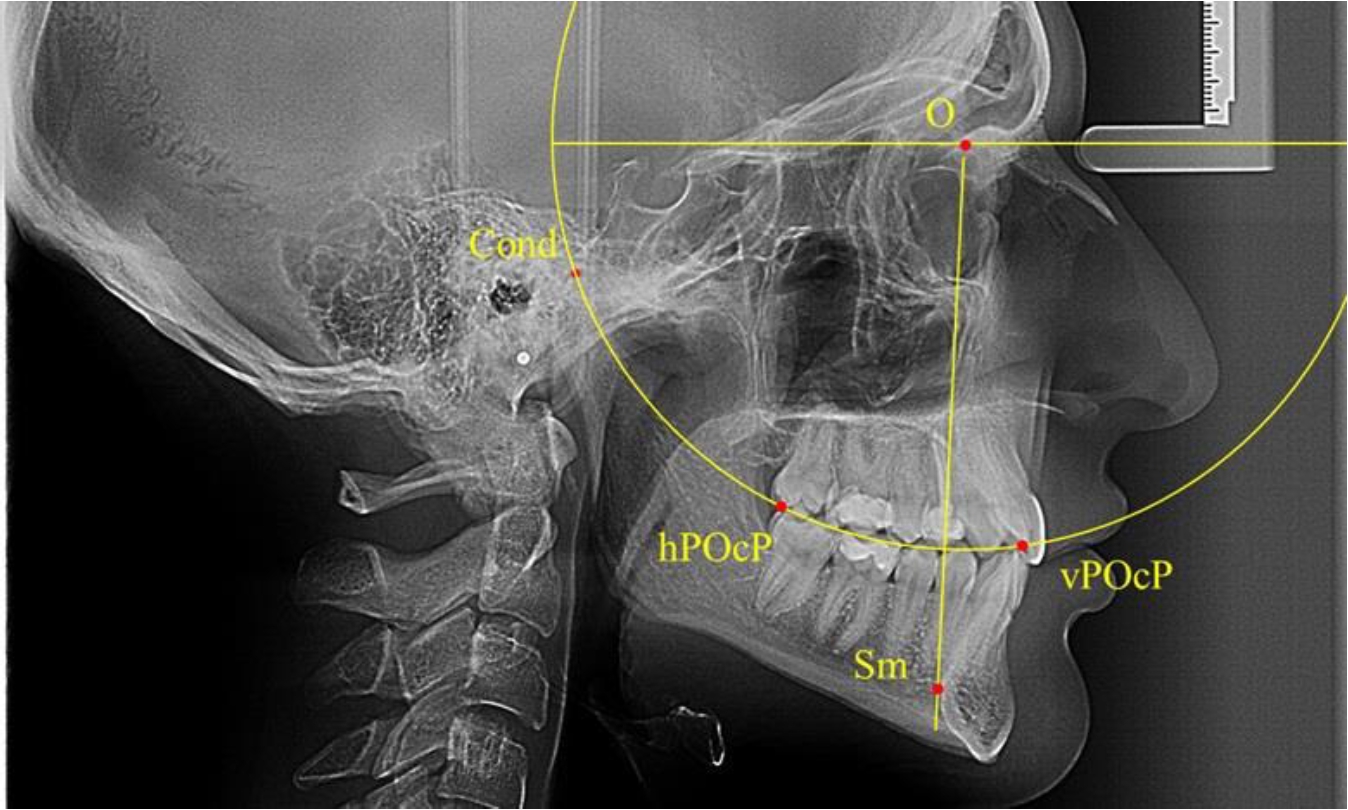

Анализ снимков проводили с использованием традиционного построения стресс-оси по Bimler. Для удобства построения использовали компьютерную программу PowerPoint. Основными точками для построения круга были передняя (vPOcP) и дистальная (hPOcP) окклюзионные точки, а также верхняя выпуклость суставной головки (Cond).

Вставка из программы в виде овала накладывалась на фотографию рентгенограммы и ручным способом растягивалась так, чтобы получился круг, проходящий через обозначенные реперные точки.

Центр окружности О, соединяющей точку резцового перекрытия с жевательной поверхностью зубов и серединой суставных головок, соединяли с выступающей точкой Sm на внутреннем контуре подбородка (рис. 1).

Рис. 1. Метод анализа ТРГ по Bimler

В норме, по резульатам исследования автора, линия Bimler проходила по вертикальной оси первых премоляров, что мы также расценивали как оптимальное их расположение.

Результаты исследования рентгенограмм с мезотрузионным типом резцов показали, что линия Bimler проходила позади первых премоляров у людей с широким типом подбородочного выступа, однако окклюзия была физиологической и не требовала удаления премоляров, что носило рекомендательный характер при проведении подобных исследований при аномалиях прикуса. У людей со средними формами подбородочного выступа линия Bimler проходила впереди первых премоляров (рис. 2).

Аналогичная ситуация была у людей и с узкими вариантами подбородочного выступа.

Таким образом, при мезотрузионном типе зубочелюстных дуг расположение премоляра впереди линии Bimler при широких вариантах подбородка не может быть критерием выбора экстракционных методов лечения.

Рис. 2. Положение первых верхних премоляров при мезотрузии с широкими (а) и средними (б) размерами подбородка